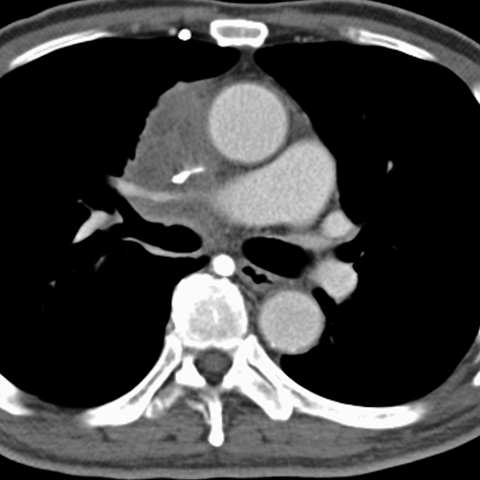

Mediastinal Lymphadenopathy, Lung Cancer (Chest CT) [3 of 3]